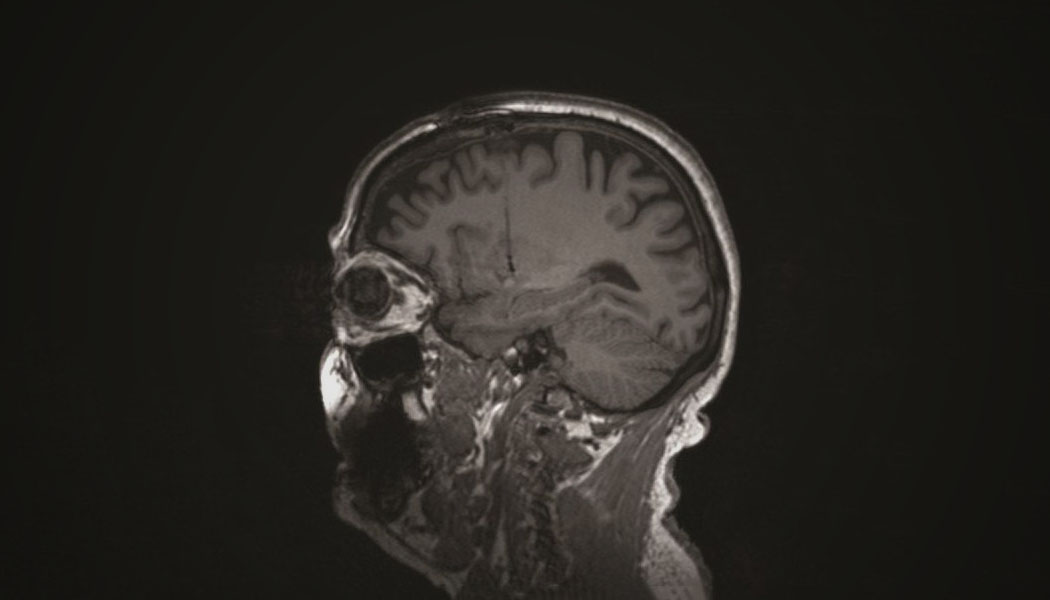

New Zealand biotech company Living Cell Technologies has developed a treatment for Parkinson’s disease using choroid plexus cells from pigs. These cells are found in the area of the brain that manufactures a mix of signaling molecules and growth factors that maintain nerve health, so the researchers transplanted the healthy cells from pig donors into four human subjects. 18 months post surgery, the results are still promising, so researchers began a placebo-controlled trial in 18 additional patients in May.

Parkinson’s disease is characterized by the progressive loss of dopamine-making brain cells. Dopamine itself helps the brain control movement in the body. The aim of this treatment is to nourish existing healthy brain cells in recipients to slow or prevent further loss. Thus far, the technique has proven successful in the treatment of rats with a species-specific corollary of Parkinson’s disease.